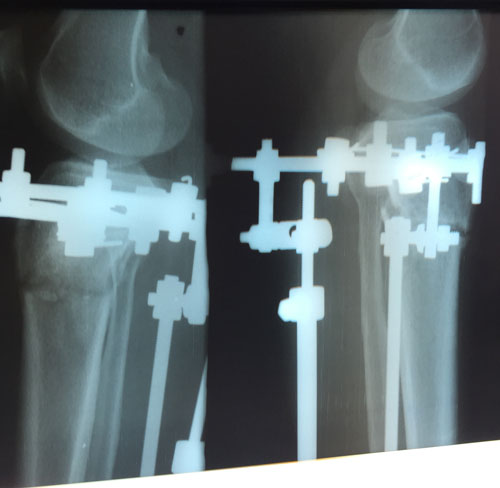

Исходник.

РЕНТГЕН ДО ОПЕРАЦИИ